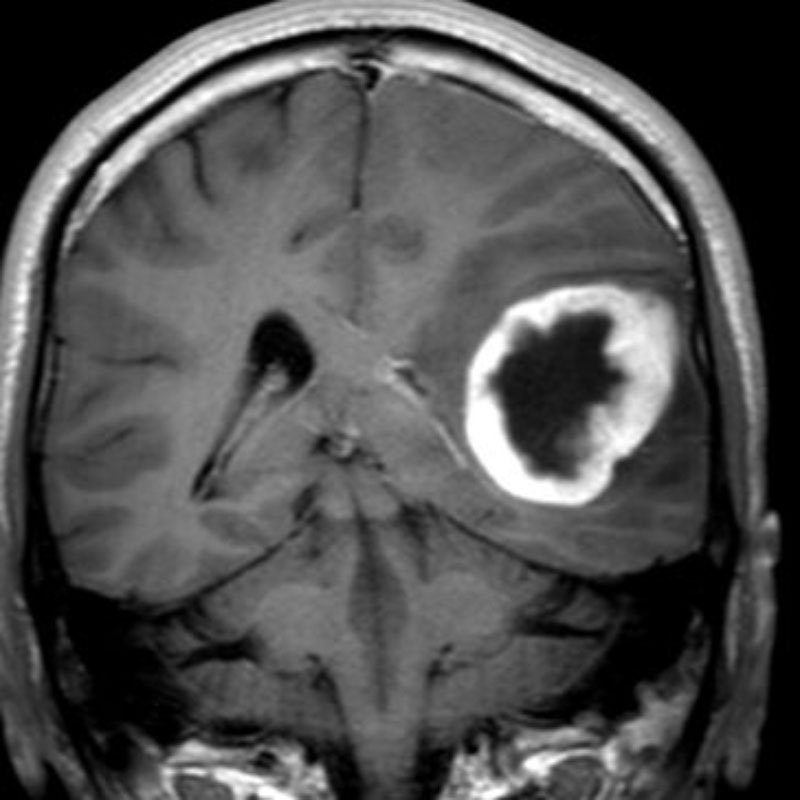

360

'22年12月

70代

右前頭葉膠芽腫

頭蓋内腫瘍摘出術

No.’22_117 手術前1

No.’22_117 手術前2